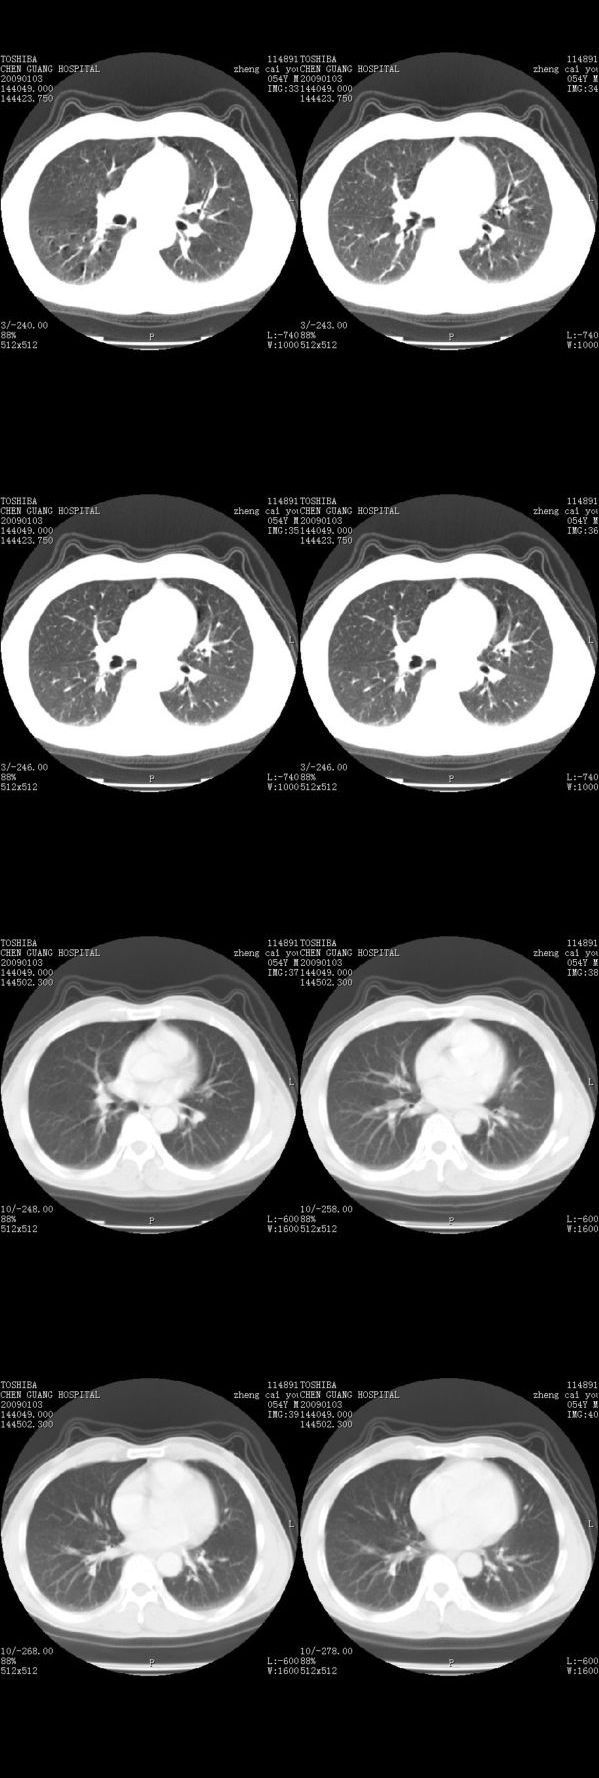

男,54岁,平时有吸烟后咳嗽、咯痰史,因右侧胸部(腋窝下)疼痛来检查平片,见右下肺动脉干起始处处结节,后到同学处做了平扫及增强。请各位老师帮忙看一下,不甚感谢!!!!!

多为血管断面影;建议必要时行ct增强扫描检查。

没有纵膈窗,也没有增强,确实不好说。从连续层面来看像是血管影。不放心做个强化最好了,毕竟是自己最亲的人!!

似乎是血管啊,连续几层都可以看见,希望高手指点迷津!!

肺窗薄扫、常规扫描均未见明确病变;右下肺门圆形与肺血管等密度影,考虑为血管变异;应该要纵隔窗才能进一步明辨。

主要应该看一下纵隔窗,感觉到右肺门的血管有局限性的扩张,呈结节状,再做个增强ct扫描.

右肺上叶前后段支气管夹角处可见一结节影,图像资料不全,不好下结论。